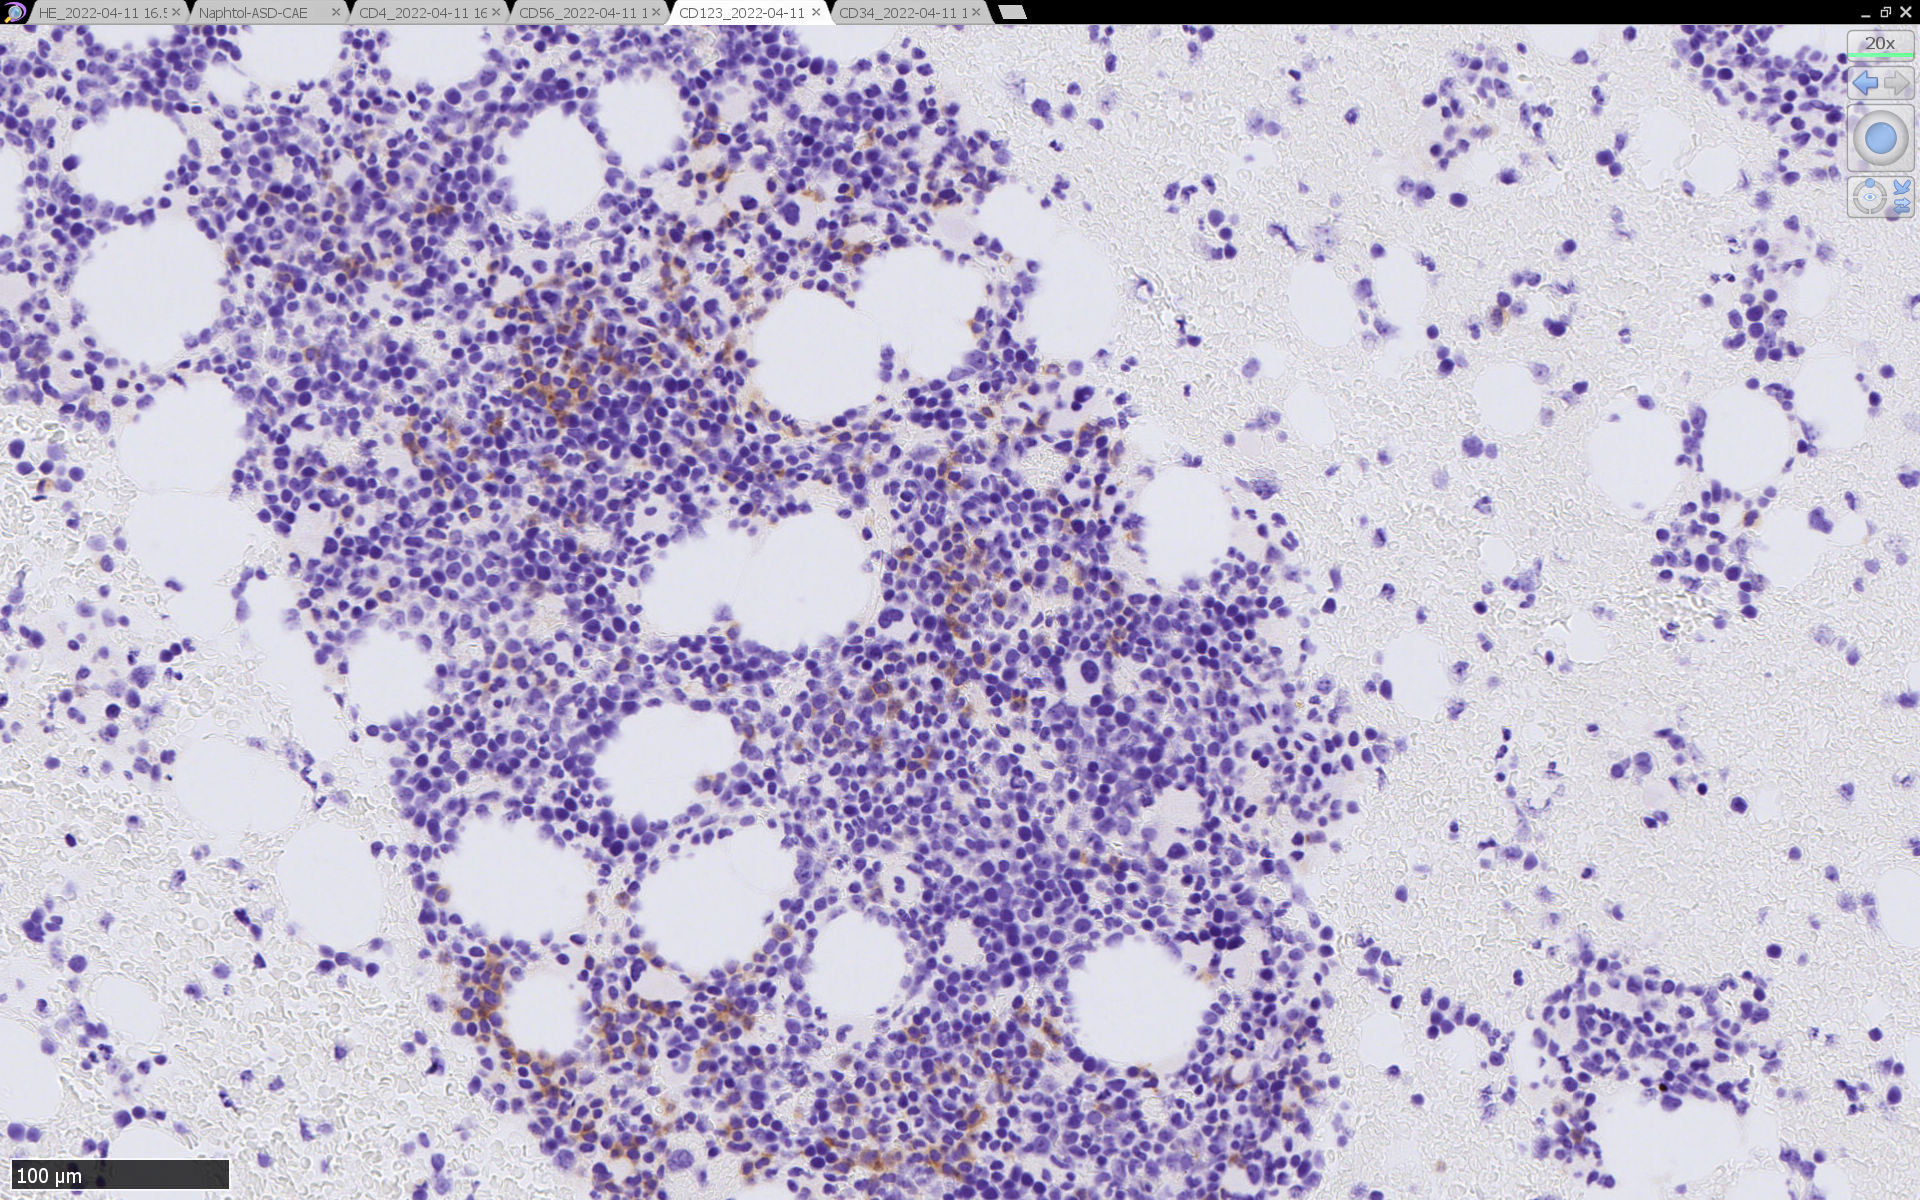

骨髄病理所見

HEでは腫瘍細胞の同定が難しい. 本症例は ASD-Giemsa染色を見ても, 腫瘍胞巣はよくわからなかった. 皮膚が先に診断がつき, 次いでBone marrowだったため, 免疫染色にすすめたが, Bone marrowが先だと診断に困ったかもしれない. 本例は, 骨髄がhypercellularで, dysplastic hematopoiesisがありMDSも疑われている.

免疫染色

CD4は染まりすぎの感がある(濃く染まる細胞はCD4+ T-cellかもしれない). CD56, CD123が陽性で可能性が高くなり, BPDCNの診断にはCD34は陰性であることが必要

TCF4、CD123、TCL1をconsultationにより染色していただき, 陽性を確認した. CD34-, lysozyme-, CD123(おいてある病院は少ないかも)をしらべて, BPDCN研究会あてconsultationをする流れでしょうか.